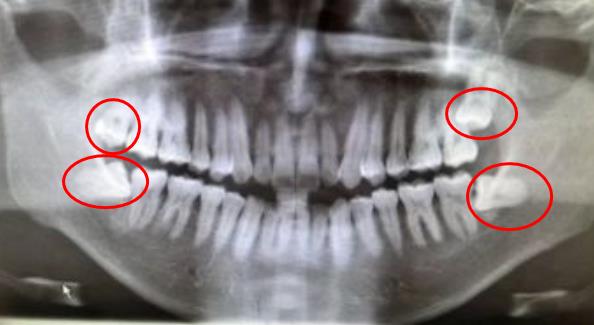

長了4顆智齒的,全景片一目了然

而且長出來的智齒數量也不是統一的,一般智齒是0-4顆, 如果全部長出就是4顆,上下左右各一顆,但是也有長3顆,2顆和1顆的。因此,具體(ti) 長幾顆這種自己不好判斷,無法確定的, 都需要到醫院拍片確定。